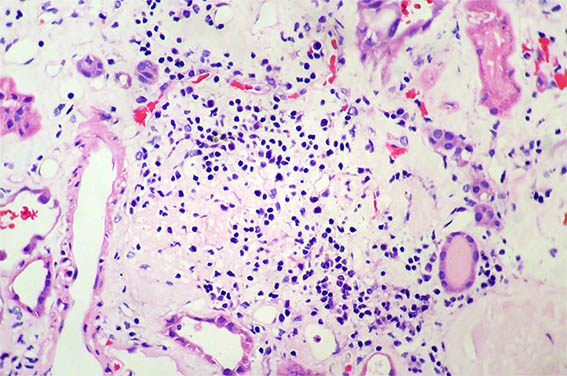

Figura 2. H&E, X200. Daño tubular agudo asociado a inflamación.